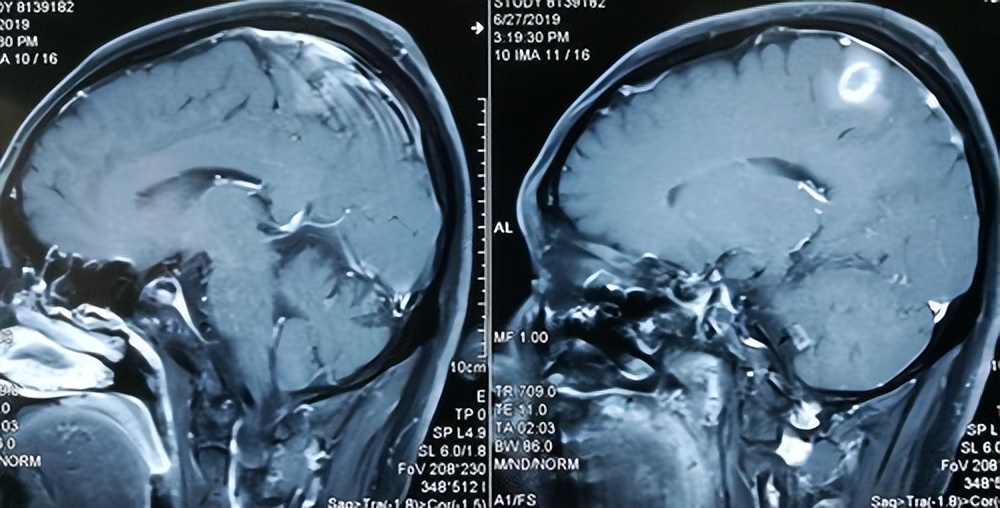

过了半个月左右,小刘的症状越来越严重了,在家人的督促下小刘来到了附近的三甲医院神经内科做检查,医生了解症状后 怀疑小刘的大脑除了问题,于是先给他开了CT检查,一个小时后检查结果出来了。

医生被吓了一跳, 在小刘的大脑脑干附近,有一个直径9cm的肿瘤病灶,与周围组织边界清晰,考虑脑血管瘤。

医生们赶紧将小刘送进了抢救室,先拍了CT, 发现小刘的脑血管瘤已经破裂出血,超高的颅内压将脑干压到了一边。